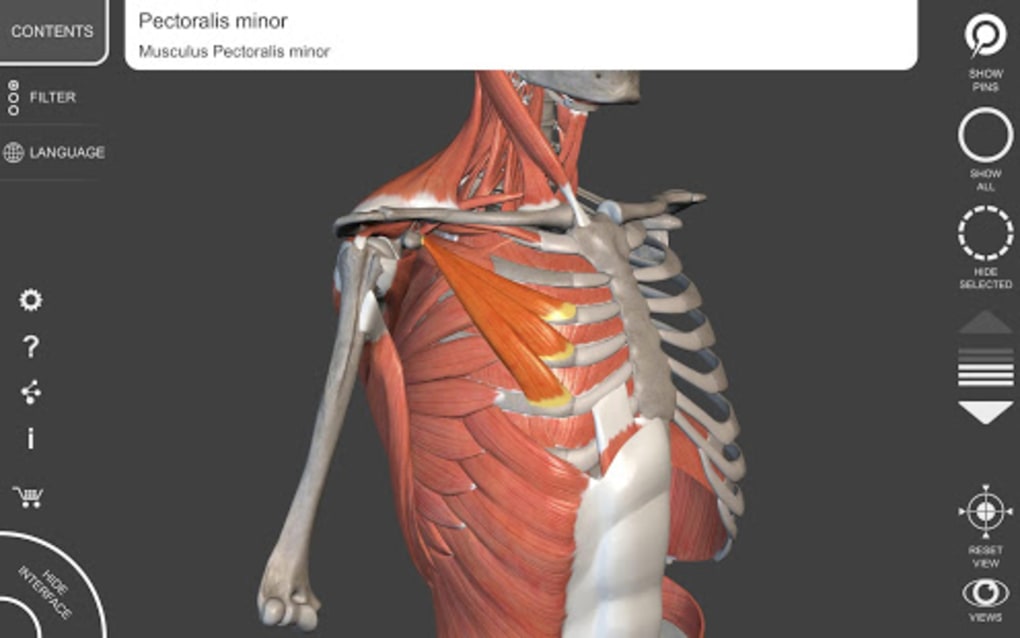

The app is based on the 3D model of the human body which is built with skeleton, muscles, bones, organs, and tissues. The anatomical models you will see in this app are the Respiratory System, Lymphatic system, Digestive System, Cardiovascular system, Eye and ear, and more.This app allows you to view the anatomy from a variety of angles, which makes it easy to study and understand.